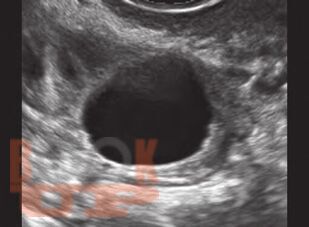

The book discusses in detail the use of Doppler for the differential diagnosis of different endometrial and myometrial lesions, ovarian and tubal lesions. The important role of Doppler for deciding stimulation protocols for patients on assisted reproductive technology treatment, for assessment of functional maturity of follicles and endometrium and also correlation of these Doppler changes with hormonal level fluctuations has also been described. This is truly a to the point, easy-to-read and reference book for the role of Doppler in Obstetrics and Gynecology and Infertile patients. Proved to be of great help to the cliniciansgynecologists and radiologists as a practical guide and a quick reference for the use of Doppler technology for better diagnosis with ultrasound.